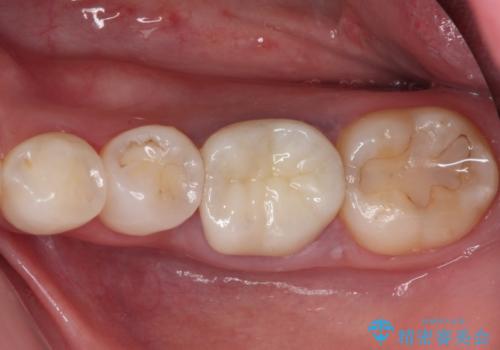

口腔内から、土台も含め銀歯がなくなったことでメタルフリーとなりました。